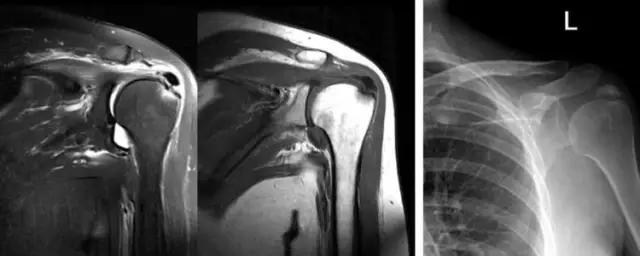

很多时候由于种种考虑,我们仅进行了MRI检查,忽视了日常的X线检查,对于经验不多者有时候DR反而更为直观。 病例:邬XX,女,35岁,左肩关节疼痛、活动困难1周。 MRI:冈上肌上方低密度影,周围水肿严重。DR:肱骨大结节上方大块高密度影。诊断:钙化性冈上肌腱炎。